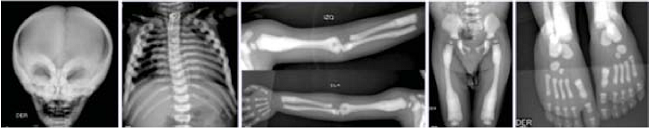

Seis meses después es hospitalizada por una segunda neumonía de origen bacteriano, además se detectó hipocalcemia de 2.5 mg/dL, por lo que la paciente requirió bolos de gluconato de calcio y calcitriol. Durante su revaloración se documentó atrofia óptica bilateral, ceguera, hipoacusia bilateral y hepatoesplenomegalia, todos hallazgos sugestivos de osteopetrosis. Con las radiografías se confirmó el diagnóstico, esclerosis difusa generalizada e imágenes de “hueso en hueso” característicos de esta enfermedad (Figura 1).

Niño de 5 años 7 meses, originario de Chiapas, con antecedente de una hermana que murió a los 6 meses de edad sin causa determinada, pero los padres refirieron que tuvo el mismo cuadro clínico. Fue enviado con el diagnóstico de osteopetrosis a los 11 meses al Instituto Nacional de Pediatría. A su ingreso se documentó peso de 6950 g (percentil -3) y talla de 65 cm (percentil -3), dismorfias faciales, fontanela anterior amplia, endotropía de ojo izquierdo, implantación baja de pabellones auriculares, puente nasal deprimido, micrognatia, pectus excavatum, cardiomegalia, hepatomegalia (4 cm debajo del borde costal), hipotonía severa y retraso psicomotor. Sus laboratorios mostraron anemia de 6.4 g/dL, trombocitopenia de 13 000/mm3 e hipocalcemia de 3.2 mg/dL. Se transfundieron plaquetas y paquete globular, además de administrar suplementos de calcio. Se documentaron las siguientes alteraciones radiográficas con las que se confirmó el diagnóstico de osteopetrosis: osteoesclerosis en base de cráneo, región periorbitaria, columna vertebral (vértebras en sándwich), metáfisis de fémur y huesos iliacos (figura 1). Durante su evolución cursó con múltiples neumonías tanto bacterianas como virales. Otra complicación fue hipertensión arterial pulmonar y cardiomegalia asociadas con tórax restrictivo. Con la misma metodología empleada en el caso 1 se determinó una mutación heterocigota compuesta en el gen TCIRG1 (OMIN *604592). La primera (encontrada en estado heterocigoto en la madre) fue una inserción de un solo nucleótido que predice un corrimiento del marco de lectura en la secuencia de aminoácidos (p.Gly159Argfs*68; NM_006019.3:c.474dup). La segunda (encontrada en estado heterocigoto en el padre) fue una duplicación de 29 nucleótidos en el exón 12, que predice corrimiento del marco de lectura en la secuencia de aminoácidos y codón de paro prematuro 79 aminoácidos río abajo (p.Phe459Leufs*79; NM_006019.3:c.1348_1376dup). La detección de las dos mutaciones en los dos alelos es compatible con el cuadro clínico de osteopetrosis, sumada al antecedente de una hermana menor con la misma sintomatología.

Los hallazgos radiológicos característicos incluyen marcado aumento en la densidad ósea con remodelación metafisiaria y apariencia de "hueso dentro de un hueso" (hueso menos denso sobre hueso más denso). La esclerosis focal de la base de cráneo y pelvis pueden presentar alternancia de bandas escleróticas, llamadas de “Lucent”, y placas en las vértebras (vértebras "sándwich"), típicas de formas adultas menos graves. La tomografía computarizada se puede utilizar para evaluar la vía óptica y el conducto auditivo, así como la efectividad del tratamiento. Otros datos clínicos son hipotrofia, mal estado general y atresia de coanas.1),(3),(10